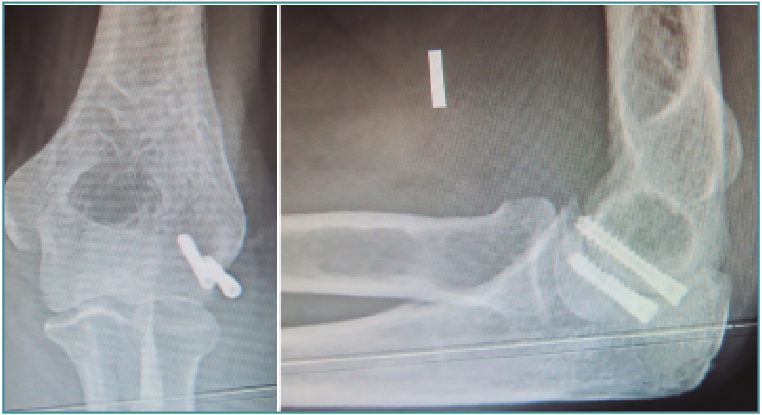

Las fracturas que se presentan con una mínima inflamación son susceptibles de fijación artroscópica asistida. El hematoma y los restos articulares se eliminarán y usaremos una o varias AK para reducir la fractura percutáneamente (Figuras 9 a 12) colocando a continuación tornillos canulados en la columnas medial o lateral del húmero. Se debe usar el fluoroscopio para evitar introducirlo dentro de la fosa olecraniana(11).

Figura 9. Radiografías y tomografía axial computarizada de fractura supraintercondílea.

Figura 10. Colocación del paciente, visión articular de la fractura y reducción artroscópica.

Figura 11. Fijación interna con 3 tornillos canulados, control por escopia y artroscópica.

Figura 12. Resultado final.